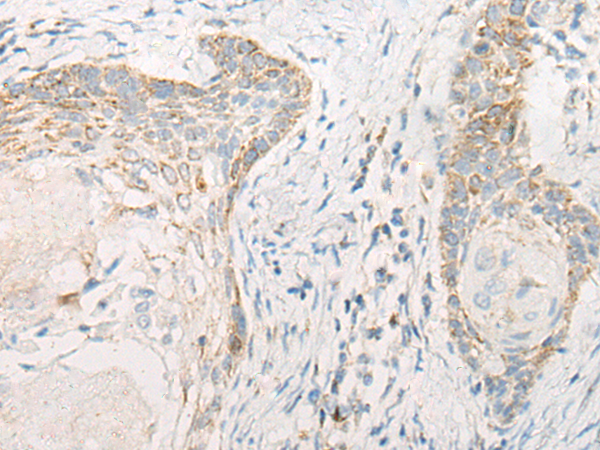

分类: 科研抗体货号: P06385别名: SCDO1应用: IHC反应种属: Human